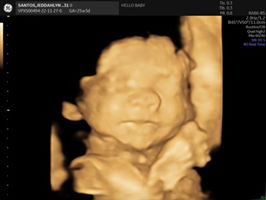

Ask ko lang po normal po ba yung result ng ultrasound ko? Wala man lng kasi sinabi yung ob about sa kalagayan ni baby.. ang sabi lng babae daw anak ko.. thanks po sa sasagot.. first time mom po ako don't judge me po

yes mie normal lng si baby

all normal mi